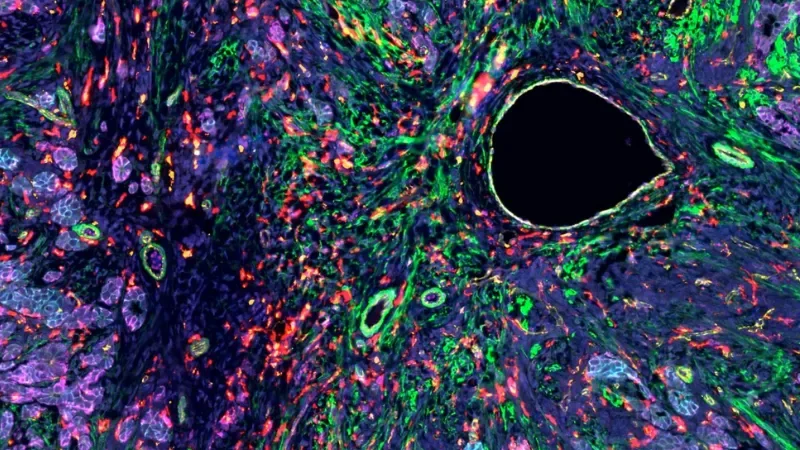

This image reveals the single-cell spatial transcriptomic map of the human endometrium (the inner lining of the uterus), collecting during the “receptive phase” of the menstrual cycle—the brief window when the endometrium is primed for embryo implantation.

This image was generated using the Xenium platform (10x Genomics), available at the JAX Single Cell Biology Lab (SCBL). The assay detects up to 5,100 genes directly in intact tissue through probe-based cyclic imaging. When paired with antibody-based protein detection—either on Xenium or the complementary Phenocycler Fusion 2.0 (Akoya) platform at SCBL—it enables true multi-omic phenotyping of tissue architecture.